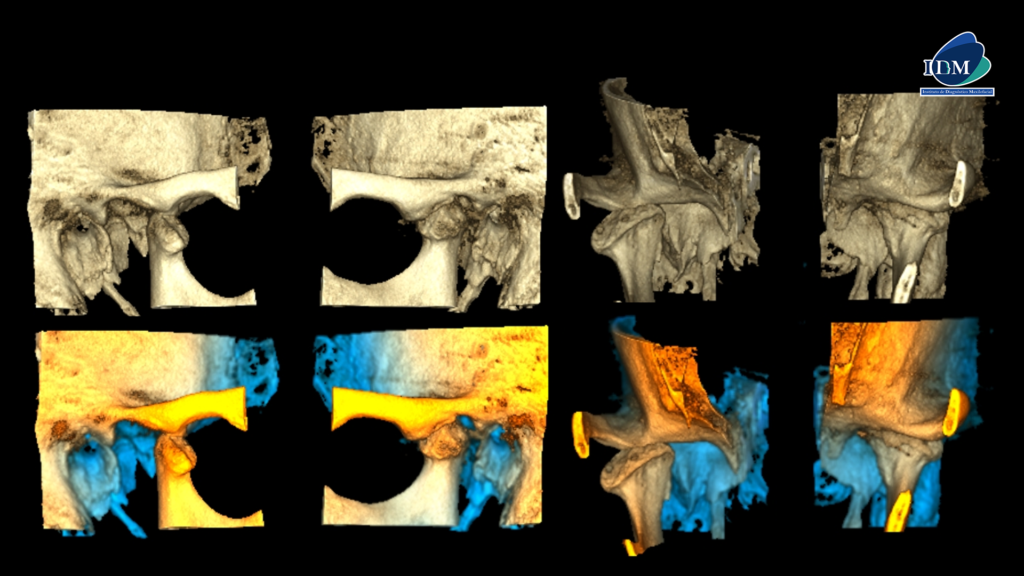

RECONSTRUCCIÓN 3D

Así mismo en la tomografía volumétrica de haz cónico a boca abierta se evidencian osteofitos anteriores en ambos cóndilos mandibulares con disminución severa del espacio interarticular, sumado a la alteración de la morfología y estructura condilar. Finalmente, se evidencia una deformación de las vertientes de ambas eminencias articulares.